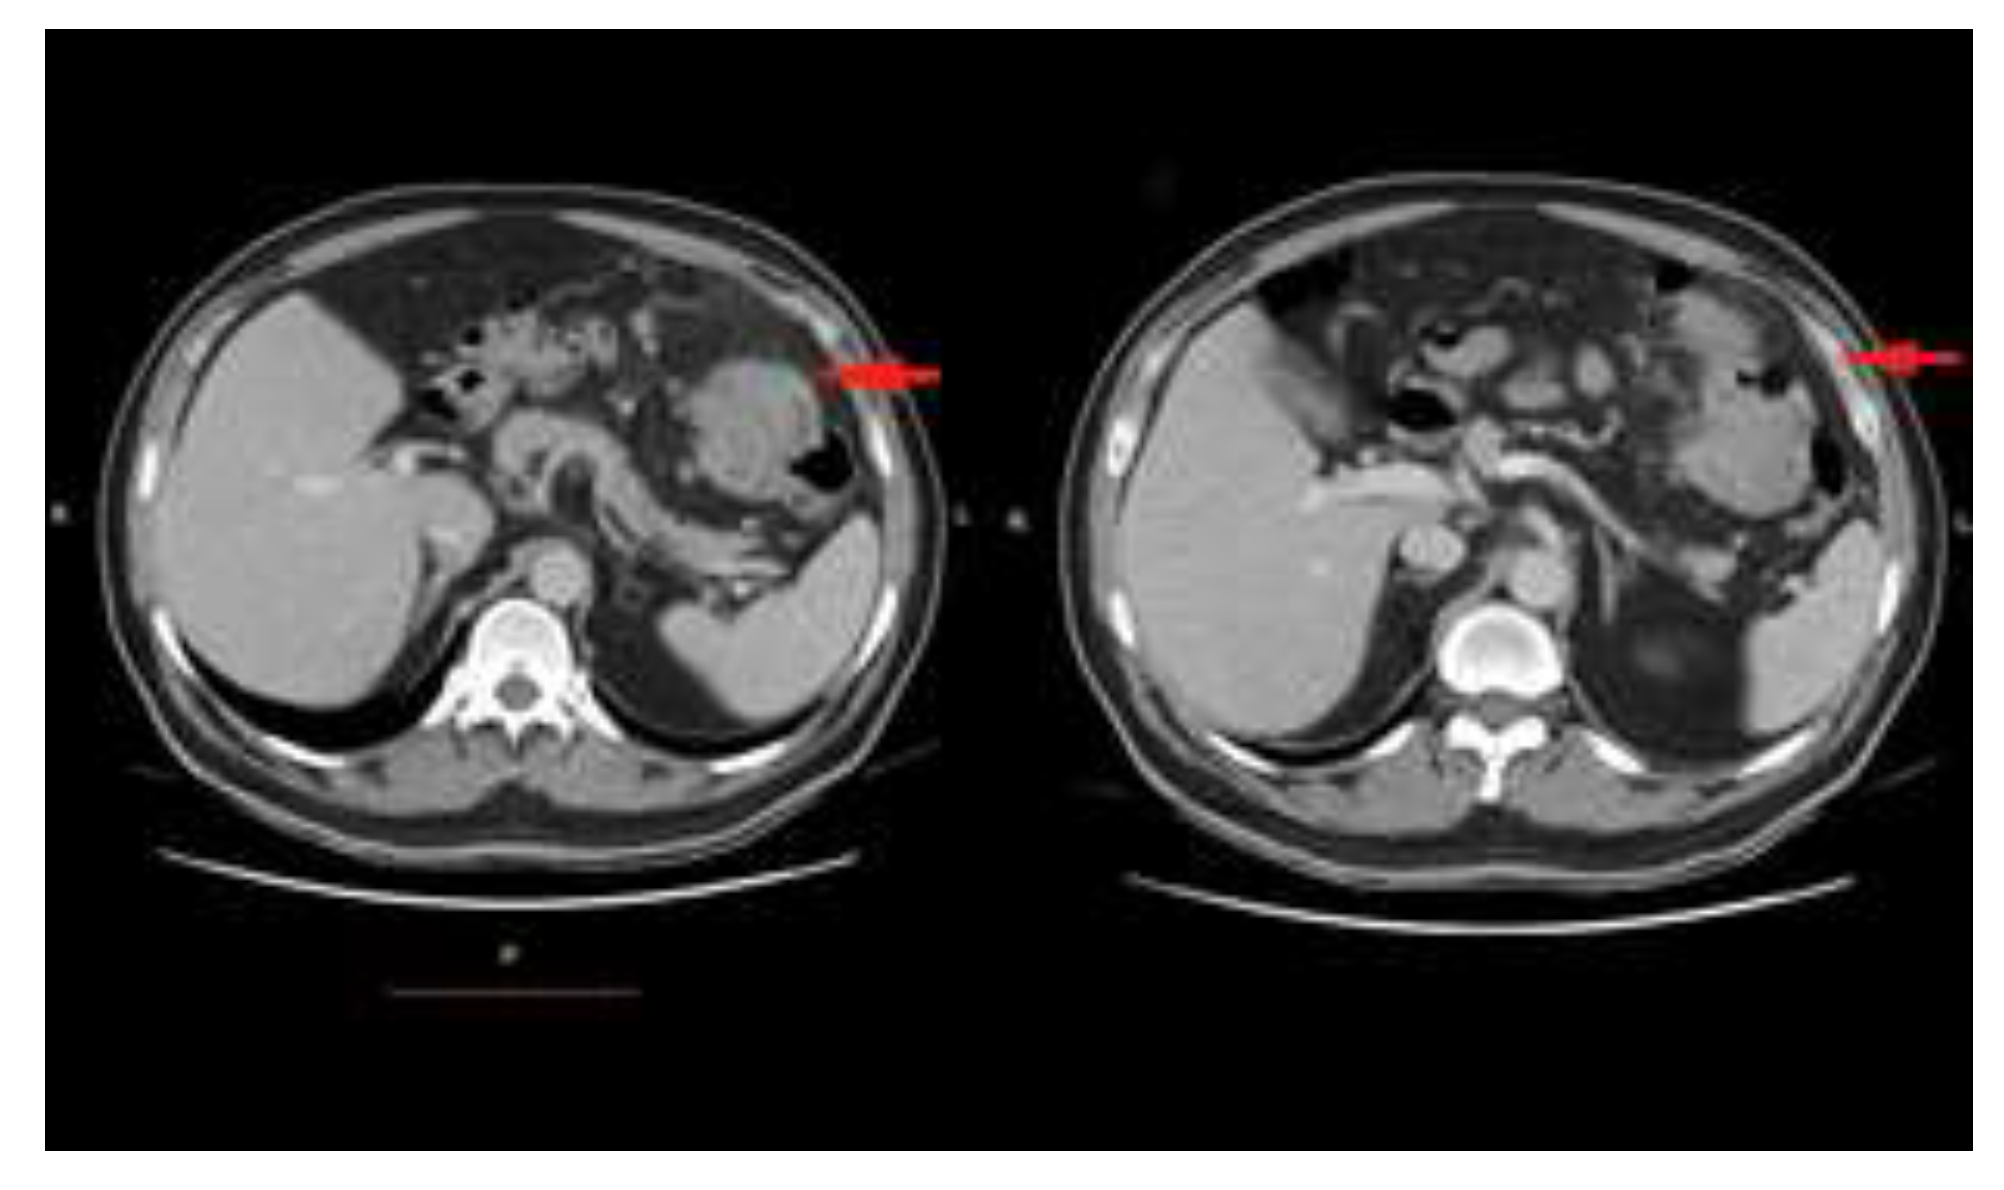

Case presentation